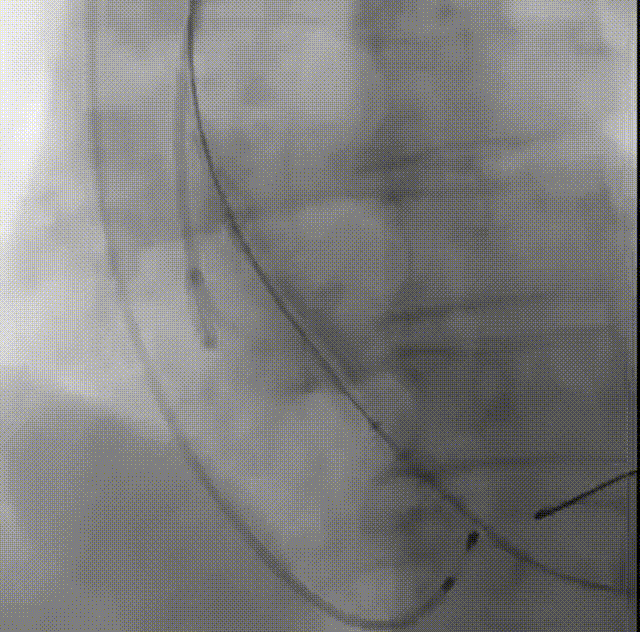

罗建方教授 广东省人民医院(点击查看专家详细简历) 设计本为临床需,耐久守护好芳华:任何医疗产品的设计初衷与最终归宿,都应落在 “临床获益” 这一核心上。尤其在 TAVR 领域,年轻患者预期寿命长,术后瓣膜的长期性能直接关乎其生活质量与生存预后。瓣膜耐久性问题,是落到临床实践中亟待突破的关键课题。传统瓣膜在长期使用中,可能因结构老化、功能退化等问题,难以满足年轻群体数十年的健康需求,二次手术风险也随之攀升。因此,产品设计必须直面这一临床痛点:通过材料革新增强抗钙化性能及生物相容性,以技术突破延长瓣膜有效使用寿命。此次临床应用的预装干瓣Prostyle A®是TAVR领域的革新理念,干瓣预期会为临床提供更耐久性的保障,实现了与临床需求的精准对接,为年轻群体的瓣膜治疗提供更坚实的保障。 李捷教授 广东省人民医院(点击查看专家详细简历) 干瓣技术求革新,性能兼顾护临床:干瓣的技术革新在创新的同时需要和临床实际需求深度耦合,兼顾TAVR术中的核心考量点。临床操作中,瓣膜能否顺利过弓,直接影响手术效率与安全性。Prostyle A®短瓣架设计及第二台阶的柔顺设计,术中操作丝滑;同时,瓣膜植入后的径向支撑力必须平衡得当,才能实现稳定锚定;释放后造影显示:瓣膜形态舒展,轻度瓣周漏,舒张压升高,冠脉开口未受影响;瓣周漏是影响术后效果的关键隐患,双层裙边设计通过多重密封机制降低反流风险,为患者长期获益筑牢防线。这些性能的协同优化,最终目的是让干瓣在临床中真正做到 “好用、耐用、安全用”,为患者预后提升提供坚实支撑。 患者病史 患者因 “活动后气促伴头晕 2 月” 入院。 现病史:2月前无诱因出现活动后气促,休息后缓解,伴头晕,夜间阵发性呼吸困难。超声检查发现:主动脉瓣重度狭窄并重度返流(跨瓣流速 4.3m/s,峰值压差 73mmHg);主动脉 + 冠状动脉 CTA 提示主动脉瓣显著钙化,升主动脉及分支粥样硬化,冠状动脉轻度狭窄(RCA 狭窄 30-40%)。 既往史:高血压病史 15 年,规律服药,血压控制稳定。 术前诊断:非风湿性主动脉瓣狭窄伴关闭不全(重度)、心功能 II 级(NYHA)、高血压病 2 级(高危)、冠状动脉粥样硬化。 术前CT 三叶瓣,瓣叶增厚中度钙化,右无交界钙化粘连,瓣环径25.1mm,LVOT 25.1mm,直筒型结构;窦部空间足够,升主未见增宽,瓣环水平夹角55°;冠脉开口位置佳,无冠脉风险;入路散在钙化、外周双侧入路无明显迂曲,双侧内径可、中分叉,左右侧均能够支持20F 大鞘通过。 造影角度及入路 右窦居中位RAO 5° CAU 26° 左冠切线位LAO 11° CRA 12° 手术策略 右侧股动脉为主入路,左侧为辅助入路;使用20球囊预扩,准备AV26瓣膜,冲洗口朝向3点钟方向送入输送系统性能,初始定位真实瓣环0位释放,最终锚定约瓣下3mm,工作位评估瓣膜稳定性与冠脉情况。 手术过程 根部造影 20mm 球囊预扩无明显腰征 术中使用26号瓣膜,瓣膜释放贴边迅速 80% 工作位观察瓣膜位置良好 释放后造影显示:瓣膜形态舒展,轻度瓣周漏,舒张压由术前30mmHg升为 60mmHg,冠脉开口未受影响。 术后超声:跨瓣流速降至1.6m/s,平均压差降至5 mmHg,心功能显著改善。 Prostyle A®预装干瓣——助力临床最优化解决方案: 1. 抗钙化与耐久性:Micro-EX™专利技术提升瓣膜抗钙化能力,适配患者瓣叶中度钙化的解剖特点,为长期疗效提供保障。 2. 柔顺过弓与精准定位:短瓣架设计 + 远端超滑涂层,确保患者输送系统过弓顺畅;瓣架流入端微直筒设计,让定位贴边更迅速,减少了手术时间; 3. 80% 可回收设计:便于术中调整观察,减少起搏时间,从而减少并发症。 4. 简化手术流程:预装设计缩短操作时间,20F 大鞘兼容外周入路,降低血管损伤风险。